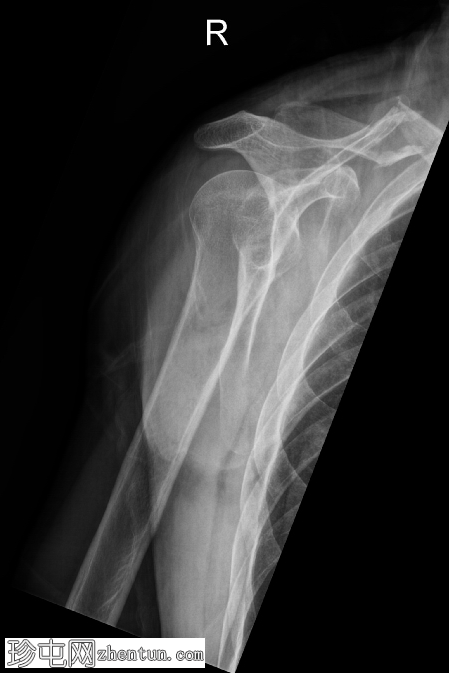

正面

右侧锁骨中段呈Z形粉碎性骨折,近端内侧骨折块向上移位,远端外侧骨折块向下移位,内侧骨折处软组织轻度膨出。

可见衣物痕迹覆盖锁骨内侧区域。肩锁关节和胸锁关节保存完好,胸腔内未见相关肋骨骨折或气胸。